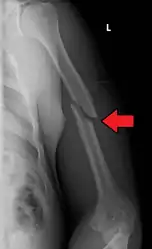

| Midshaft humerus fracture with callus formation | |

A transverse fracture of the humerus shaft

Middle

Fractures of the humerus shaft are most often uncomplicated, closed fractures that require nothing more than pain medicine and wearing a cast or sling. For midshaft fractures up to 12 weeks may be required for healing.[17]